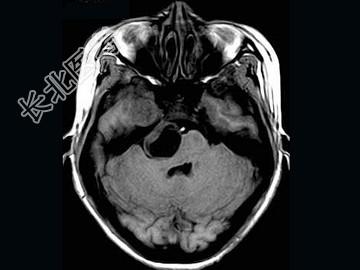

- 单项选择题女,41岁, 头痛,头晕, 走路不稳1个月余,MRI检查, 最可能的诊断为 ( )

A、听神经瘤

B、脑膜瘤

C、三叉神经瘤

D、胆脂瘤

E、神经纤维瘤